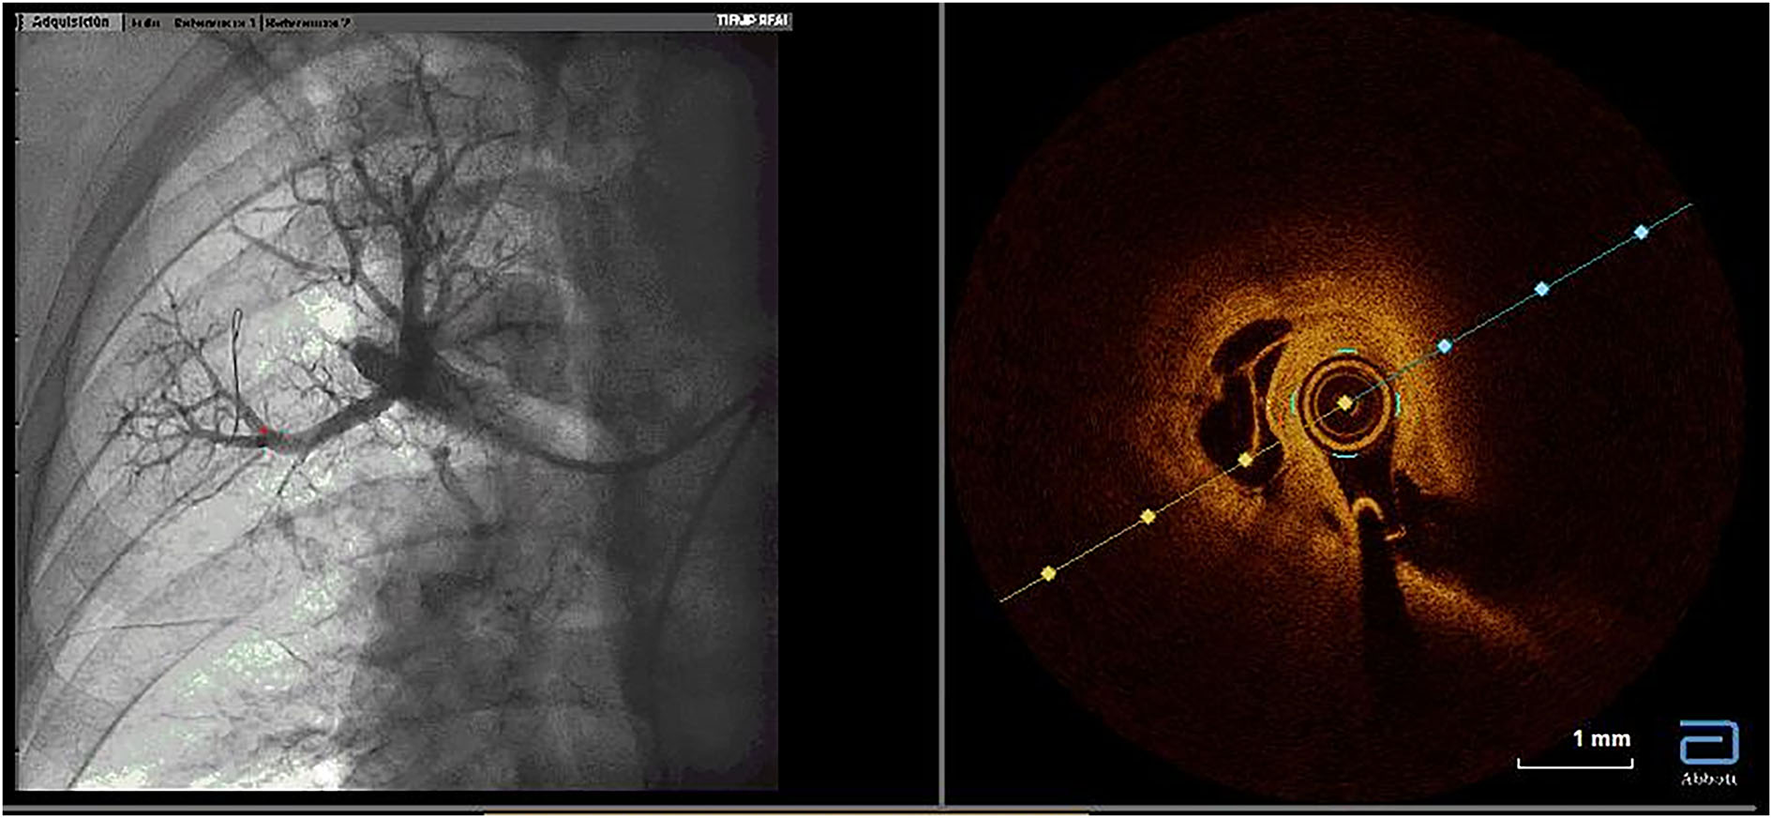

Figure 2

Utility of optical coherence tomography to confirm CTEPH organized thrombi inside pulmonary arteries. Organized thrombi inside one segmental branch of the upper right lobe. CTEPH, chronic thromboembolic pulmonary hypertension.